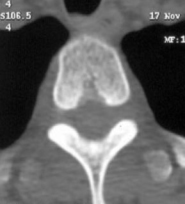

Капиллярная гемангиома

Капиллярные гемангиомы состоят из большого количества переплетающихся тонкостенных сосудов, расположенных в несколько слоев в виде «клубка» и разделенных жировой и фиброзной тканью. Данные гемангиомы редко достигают больших размеров, не дают болевой симптоматики и практически никогда не оперируются.

Капиллярные гемангиомы состоят из большого количества переплетающихся тонкостенных сосудов, расположенных в несколько слоев в виде «клубка» и разделенных жировой и фиброзной тканью. Данные гемангиомы редко достигают больших размеров, не дают болевой симптоматики и практически никогда не оперируются.